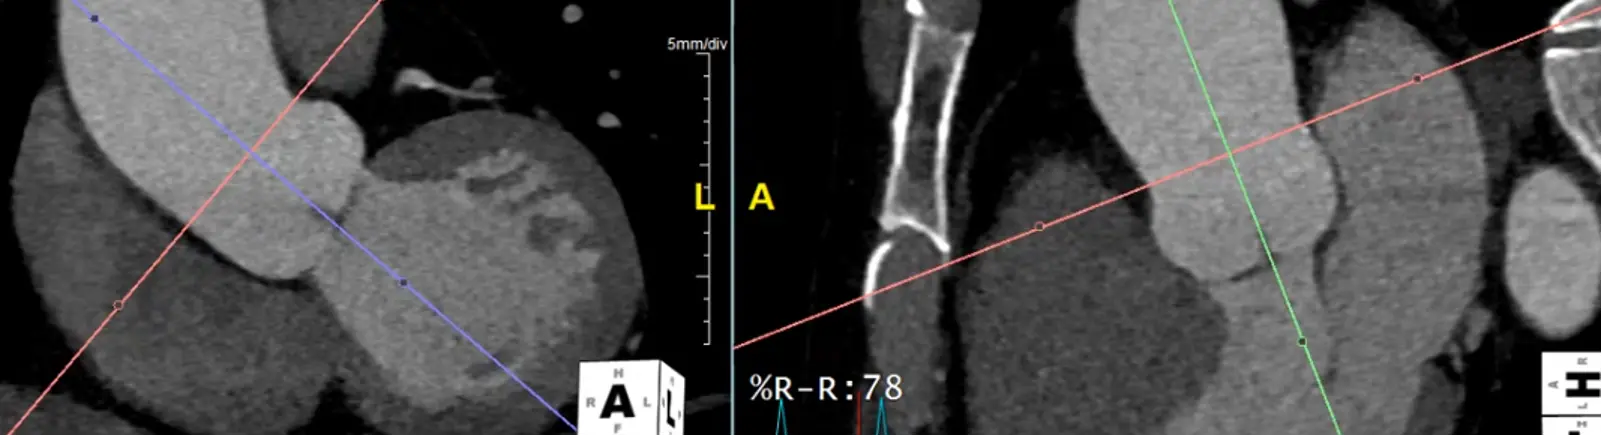

- Hit

Xto grab your cross-hairs. You will drag the cross hairs to the middle of the sinuses of Valsalva in the axial view window. - In your coronal view window, there is a pink/red line with a small circle. Drag this circle to line up the pink/red line to be perpendicular to the wall of the sinus of Valsalva. The blue/purple line should be in the center of the long-axis of the aorta at the sinus of Valsalva.

- Similarly for your sagittal view, you will want your pink/red line to be perpendicular to the sinuses of Valsalva. You will also want your green line to be in the center of the long-axis of the aorta at the sinus of Valsalva.

- Once youâve lined things up, in your axial view window you will now have what is called a âtrue short axisâ of the aorta at that level.

Measure at Sinotubular Junction

- Drag the lines to the sinotubular junction, i.e. where the sinuses and the tubule combine

- In the axial view, the âtrue short axisâ should be pretty close to appearing like a circle.

Measure at the widest segment

- The widest segment (typically) is at the mid-aorta at the level of the main pulmonary artery (MPA)

- Same as above, drag your crosshairs to the desired level and adjust to be perpendicular to the artery wall in the coronal and sagittal views. Line up the blue/green line to be in the center/parallel to the long axis of the aorta at that level.

- In the axial view, the âtrue short axisâ should appear like a circle